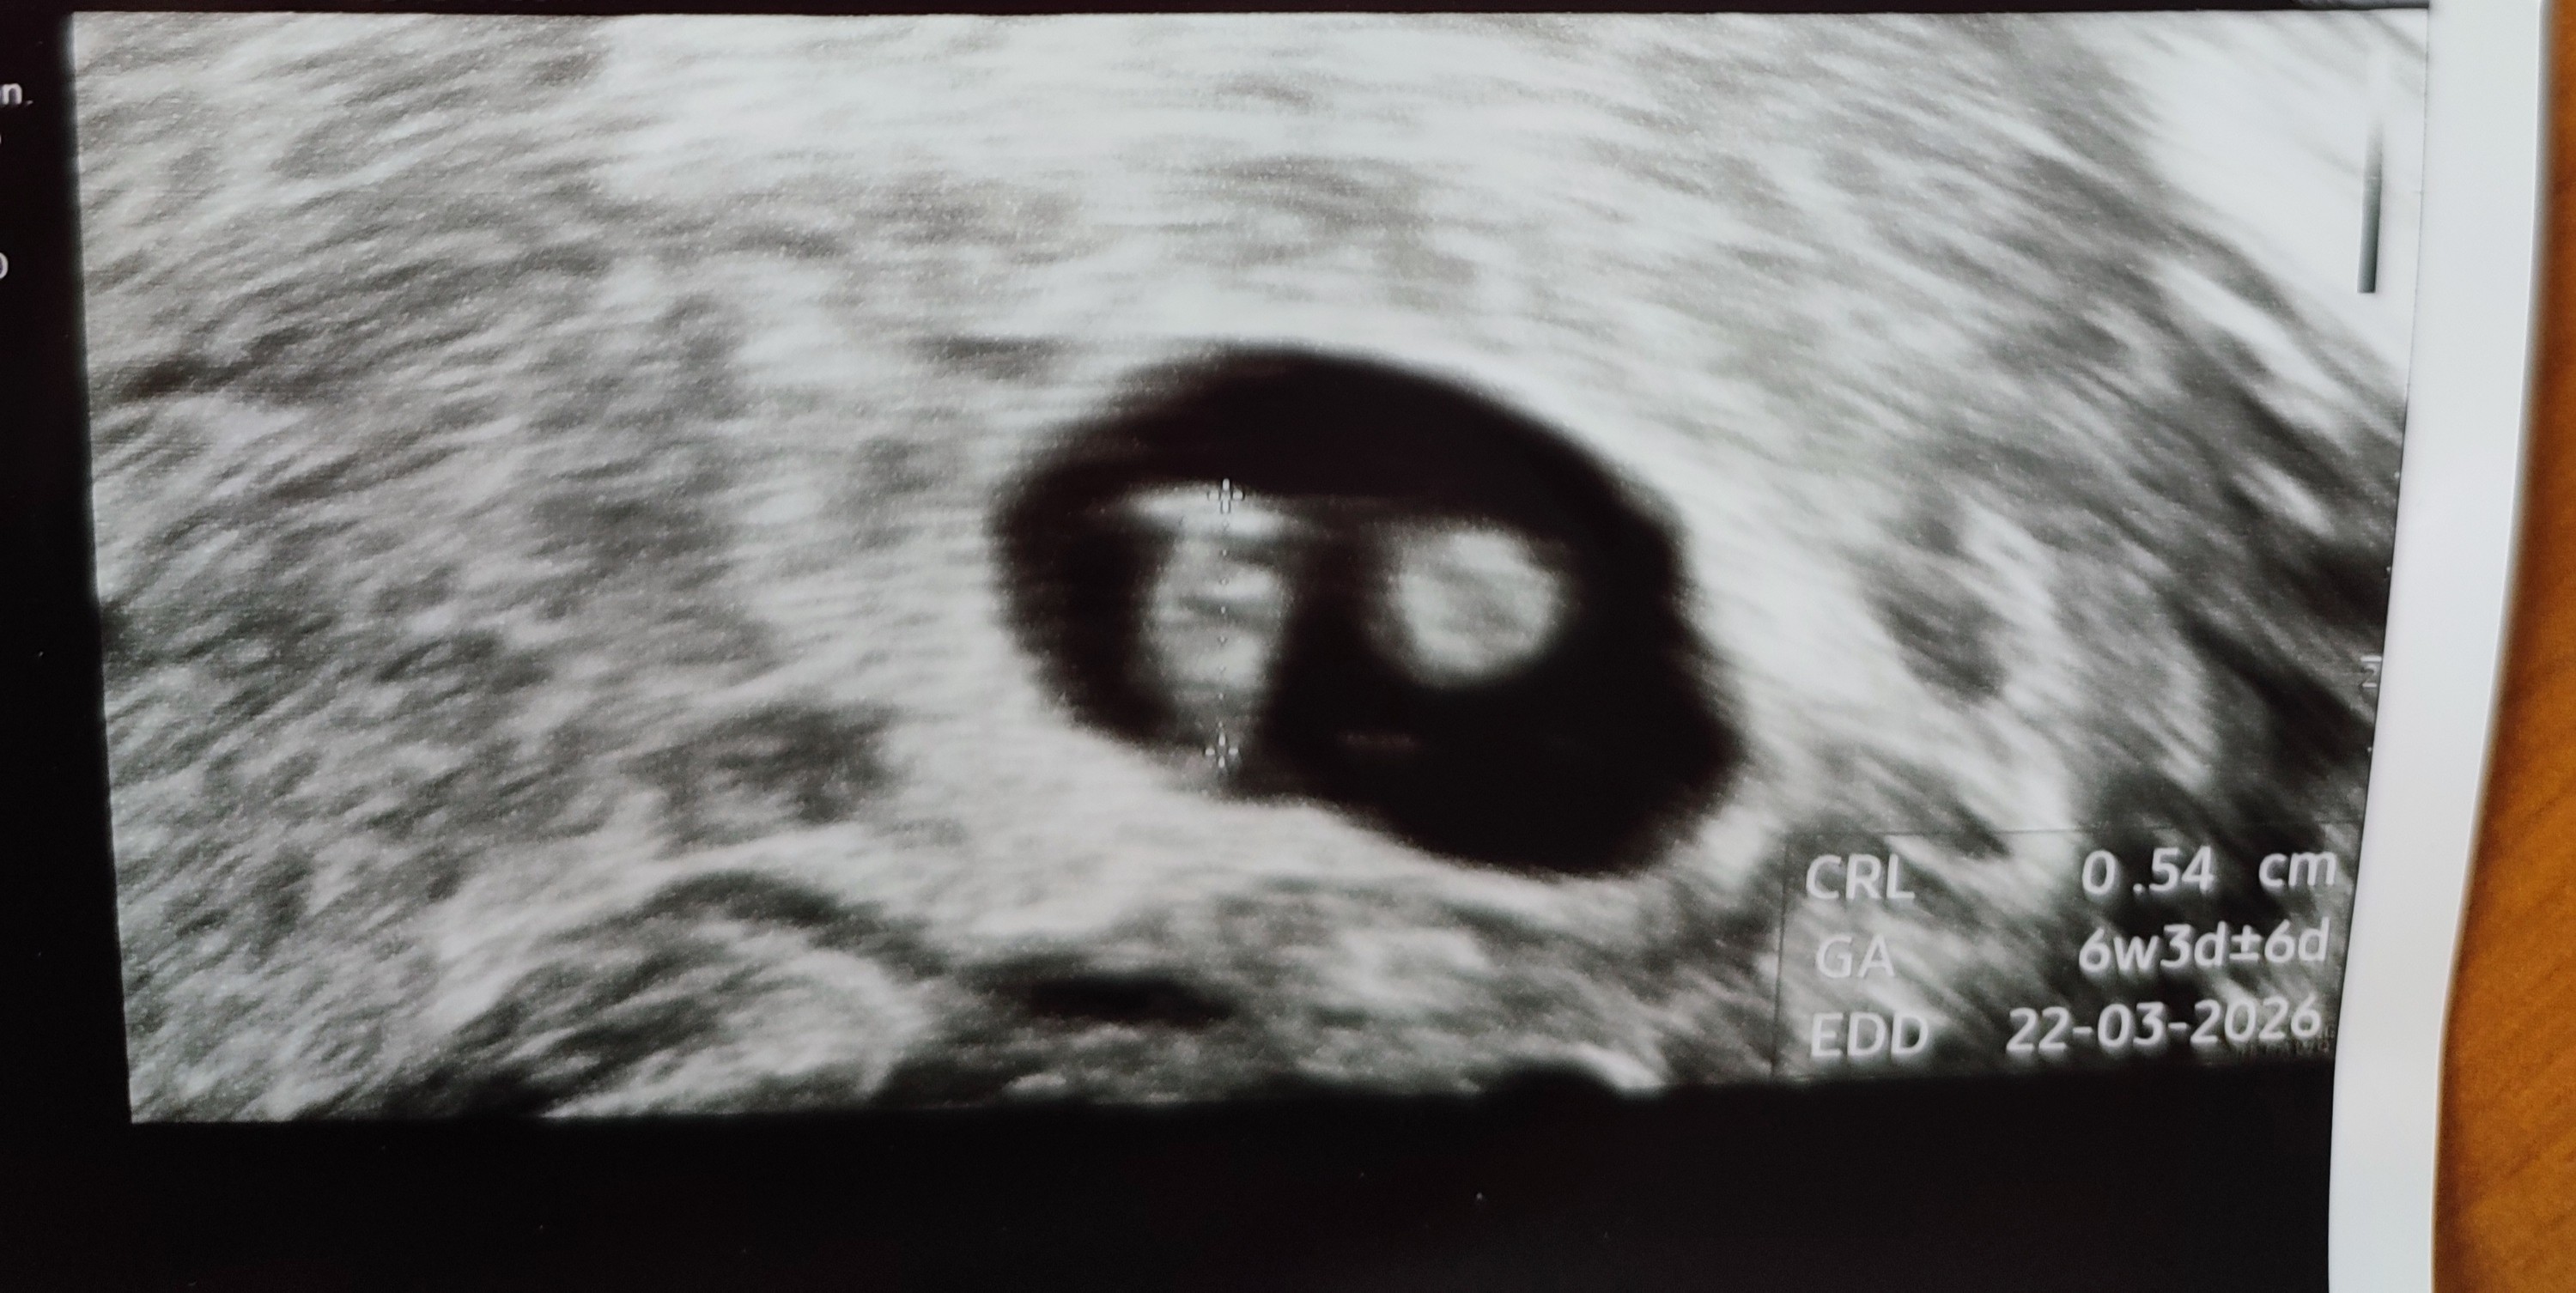

Hej, jestem już po pierwszym usg. Z OM 7+3 a z USG 7+0. Wszystko dobrze, serduszko bije, aż mi łezka popłynęła w gabinecie

Załączniki

• 4006224.jpeg

4006224.jpeg

75,8 KB · Wyświetleń: 61